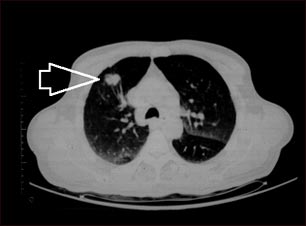

Masa pulmonar, lóbulo superior derecho - Tomografía computarizada

TC de la parte superior de los pulmones. El individuo posee una masa en la parte superior del pulmón derecho (lado izquierdo de la imagen).